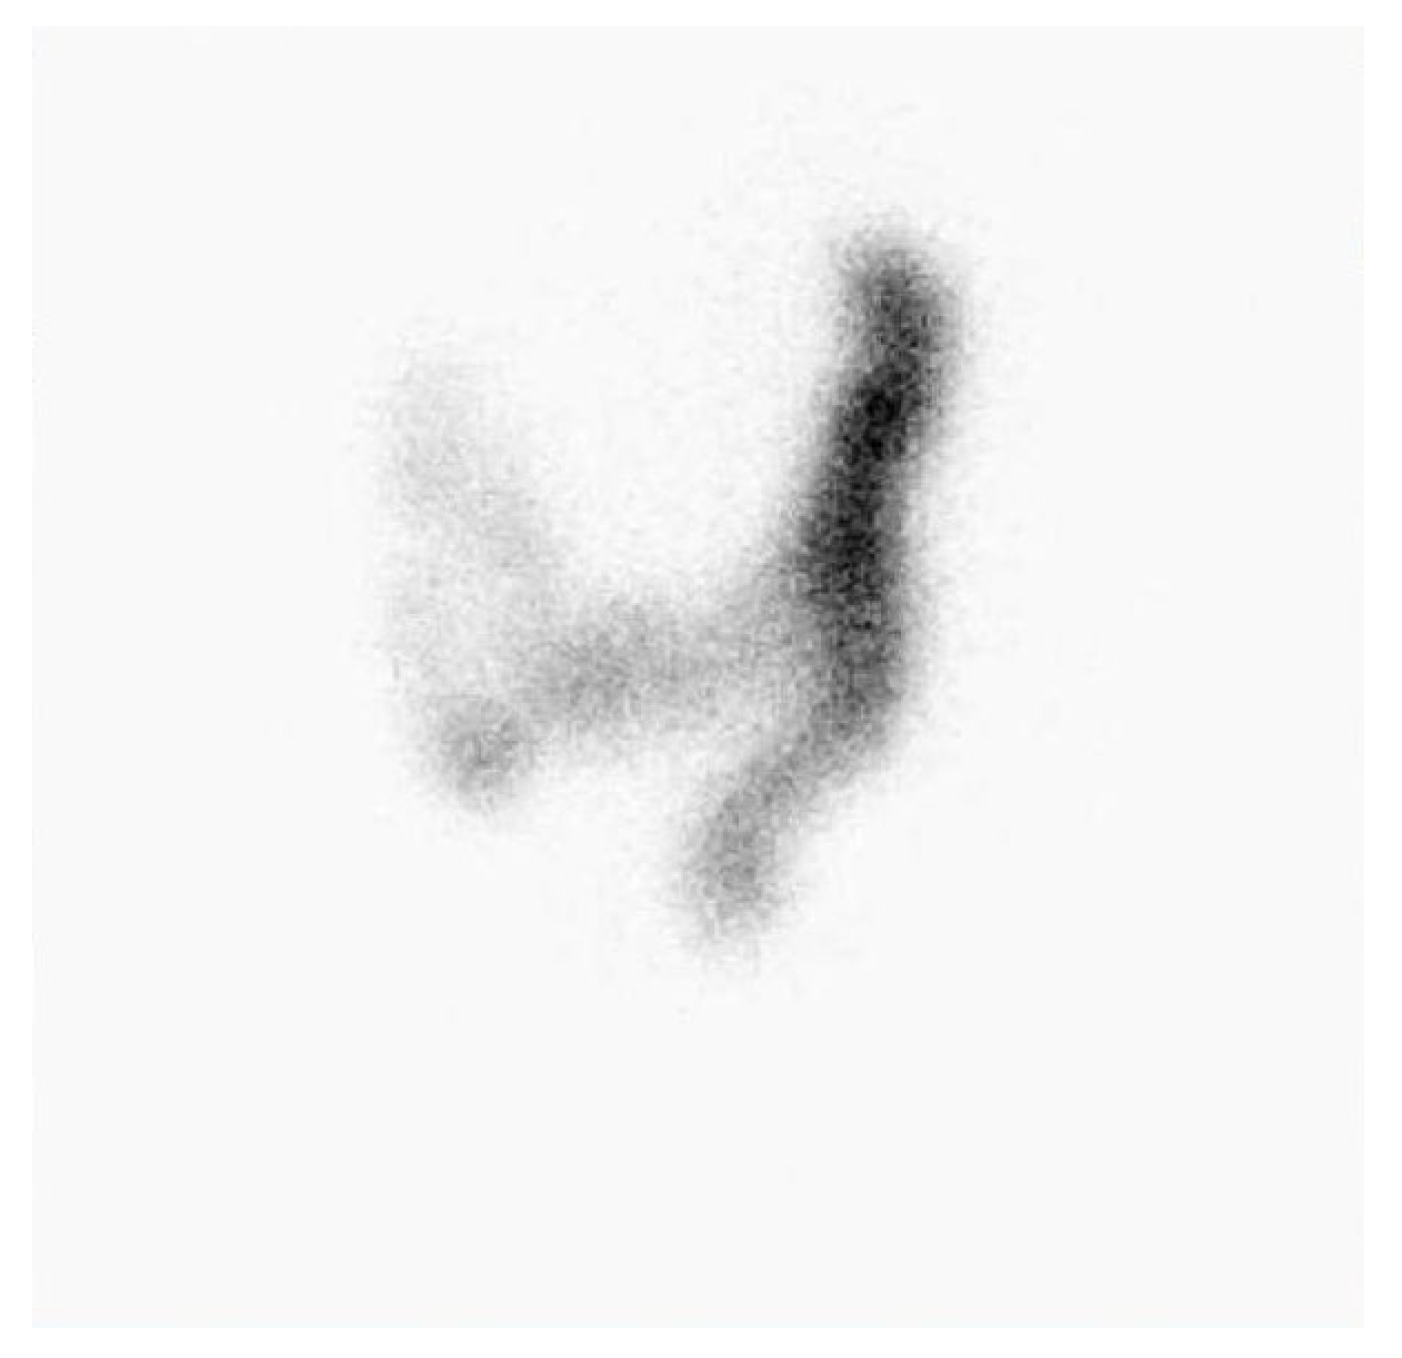

The qualitative assessment yielded the following results: The majority of examined patients with symptomatology I after self-evaluation indicating constipation showed a generalized slowed transit time through the large intestine. By general analysis between genders, it was observed that generalized slowing of colonic transit was detected more often in women compared to the male part of the examined patients. In 85% of women, a significant slowing of colonic transit was observed after the scintigraphic study, while 15% of subjects showed both qualitatively and GC-estimated normal colonic transit. In men, slowed colonic transit was detected in 78% of examined patients, while 22% of patients had qualitatively normal colonic transit and GC that fell within normal values. In women, the slowing down of colonic transit in the transverse and descending colon predominated, Figure 1 and Figure 2.

Figure 2. Static scintigram in anterior projection, 48 hours after administration of radiofarmaceutical. Female 43 years old, with constipation symptomatology. Qualitatively retention of radiopharmaceutical was observed predominantly in descending colon. GC value was 2,1.